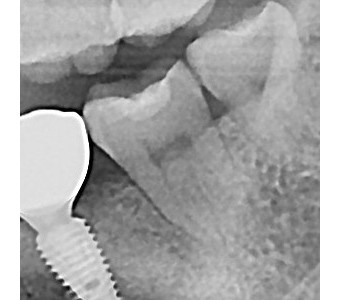

오스템 임플란트 프리미엄 BA 등급 사용

같은 오스템이라도 등급이 다릅니다. 더 빠른 골유착을 위해 프리미엄 등급을 사용합니다.

결과로 증명합니다.

국제모아치과의

실제 임상 증례